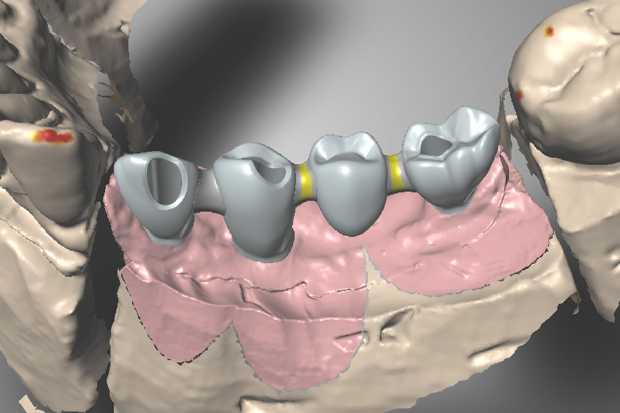

Annak érdekében, hogy a visszahúzódott állcsont miatt megnövekedett terhelésnek a fogpótlás képes legyen hosszútávon ellenállni, nem elég nagy pontossággal illeszkedni a fogimplantátumokba, speciális anyagból kell lennie. Ráadásul mielőtt elkészülne, le kell modellezni. Tudnunk kell, hogy amit szeretnénk, működni fog a szájban. Ehhez a legkorszerűbb számítástechnikát használtuk. Az eredményt az illusztráció mutatja.

A hosszútávú siker szempontjából nagyon fontos, hogy a fogpótlást tisztán lehessen tartani. Mivel a visszahúzódott állcsont miatt mélyen levő fognyakaknál ez nem könnyű feladat, olyan formát terveztünk, hogy a páciensnek ne legyen ezzel gondja. Ha pedig segítségre szorul, akkor sincs baj. Mivel a fogpótlás csavarozott, bármikor gond nélkül eltávolítható. Így rendelői körülmények közt tökéletesen megtisztítható és visszahelyezés után ismét használható.